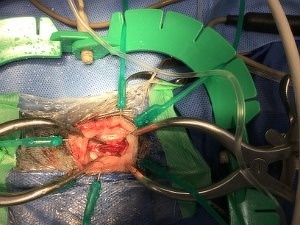

腰の椎間板ヘルニアの場合、片側椎弓切除術(ヘミラミネクトミー)という方法が一般的に行われていますが、今回は小範囲片側椎弓切除術(ミニヘミラミネクトミー)という術式で実施しました。

この方法は、視野が狭くなるため慣れないと難易度は増しますが、片側椎弓切除術よりも侵襲性が少なくすむという利点があります。

手術時、大量の椎間板物質が確認できました。

写真の椎間板物質はその一部で、出ていたものはこの3~4倍ありました。